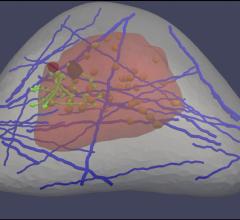

Next to lung cancer, breast cancer is the leading cause of cancer death in women, according to the American Cancer Society. That’s why so many medical professionals encourage women to get mammograms, even though the tests are imperfect at best—only a minority of suspicious mammograms actually leads to a cancer diagnosis. Recently, a different type of test, ultrasound elastography, has been used to pinpoint possible tumors throughout the body, including in the breast.

Shear-wave elastography is set to become an important tool for detecting breast cancer, as it will reduce the number of breast biopsies performed and consequently ease the healthcare burden and decrease overall disease mortality, according to an analyst with research and consulting firm GlobalData.